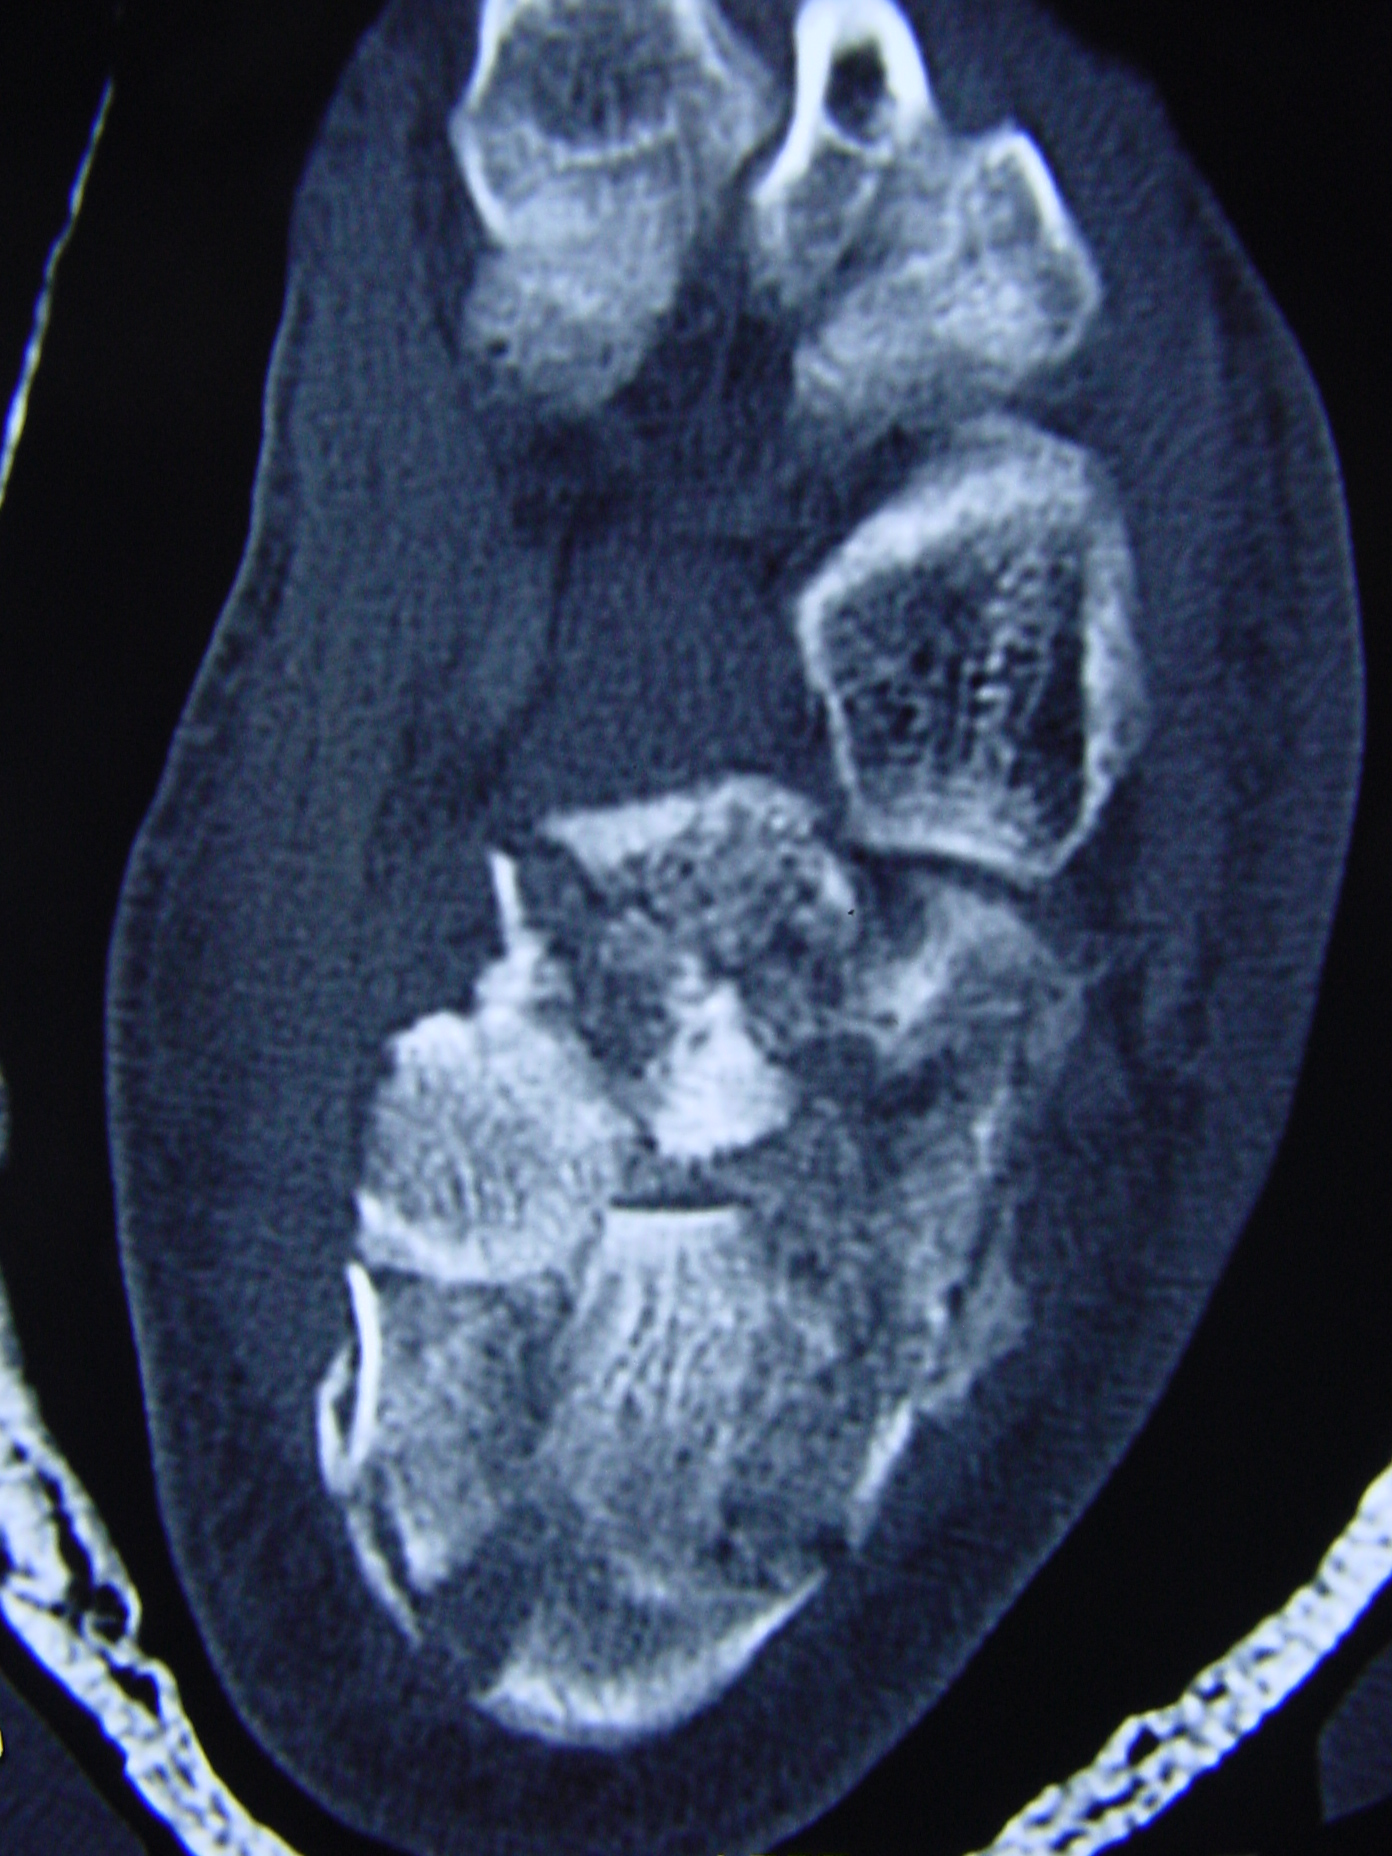

Αξονική τομογραφία της πτέρνας.

Εικόνα 2 α, β,γ,δ,ε,ζ

Ι. Εγκάρσια – οριζόντια λήψη

ΙΙ. Μετωπιαία (coronal) λήψη

ΙΙΙ. Οβελιαία λήψη (Sagittal)